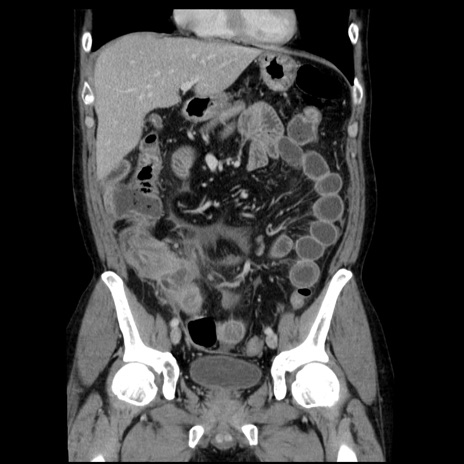

症例29(冠状断像)

【症例】40歳代男性

【現病歴】2日前から胃痛あり。徐々に周期的な激痛に変化した。本日になっても激痛があるため受診。

【身体所見】意識清明、BT 38-39℃台あり、腹部:膨満、やや硬、右下腹部に圧痛あり。

【データ】WBC 8500、CRP 23.26